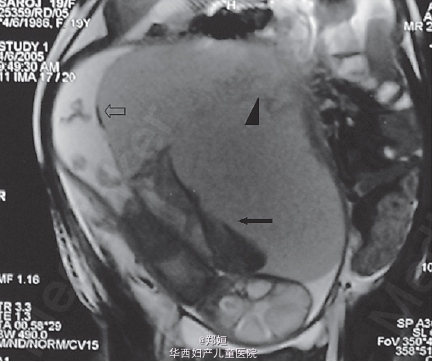

体检发现腹肌紧张,宫高高于胎龄,可触及边界不清的肿块 临床怀疑为子宫肌瘤红色样变,胎盘肿块,胎盘早期剥离 超声提示胎盘显著增大 彩色多普勒提示胎盘肿块有血流信号 由于缺乏确切的临床和超声证据,采用MRI诊断 T1相可见肿块是异质的,而其余胎盘正常 肿块呈中间信号

MRI诊断为巨大的绒毛膜下血肿 由于患者血流动力学稳定,所以继续严密观察 孕32周行剖宫产 术中可见胎盘的巨大绒毛膜下血肿25*20cm